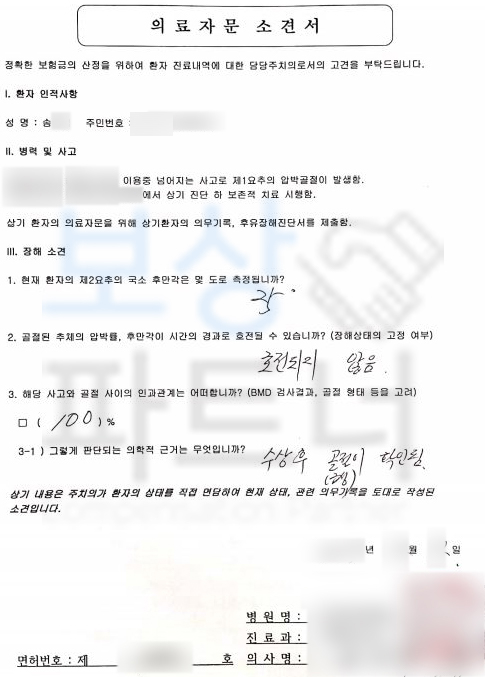

가입시기에 따른 약관의 변화와 예상 보상 범위를 말씀드린 후 사건을 수임하여 진행하게 되었는데요, 장해의 잔존을 증명하기 위해서는 의료 전문의의 후유장해 진단서가 필요한데

공신력있는 타 병원의 전문의로부터

AMA 후유장해 진단서 발급을 하게 되었습니다. 이 후 손해사정서도 함께 작성하여 각 보험회사에 청구하였는데요,. 역시나 보험회사에서는 압박률과 후만각의 의료자문을 시행하겠다며 보상파트너와 약 한달간의 분쟁을 하였지만

결국 보상파트너가 처음 청구한

척추에 뚜렷한 기형을 남긴 때 30% 영구장해

인정받게 되어